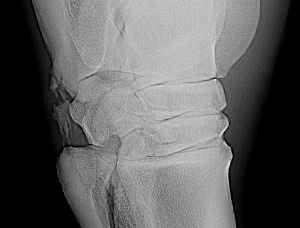

Here is one more x-ray:

Leg #4

No guarantees of what? It is nonsense to think removing badly displaced pieces that are too small to screw down is not going to result in a better outcome, including possible soundness. Even if this results in just pasture sound the horse will be more comfortable with them gone. If surgery is an option for your friend's horse I would get a second opinion from a referral center on this.

An addendum to the above. I have moved the radiograph images to a larger screen and viewing them it appears all the fragments are off the back of the talus and may communicate with the talocaneal joint (correction off the back of the calcaneus and communicates with the talocrural joint~DrO) cand have minimal effect on the stability of the joint. Does the veterinarian who has the originals agree?

Well, Janice you do help buy baby a new pair of shoes but I have to correct my anatomy above, this is most likely off the calcaneus and not the talus and communicates with the talocrural joint not the talocalcaneal joint by way of the proximal intertarsal joint. I must of had talus on the brain. The gist of my comments on prognosis and treatment still apply. I do think a flexed lateral and flexed dorsolateral-posteriomedial and a skyline view of the plantar surface of the talus would further eludicate whether the 4th tarsal bone is involved or intraarticular bone is involved.

This surgery would have to be done under general anesthesia. From a small set of limited resolution images of radiographs and not having done such a surgery myself, I have taken this about as far as I can. Unless surgery is just not an option do to financial constraints, I strongly suggest forwarding to a facility for a second opinion on this.

If the body cannot reincorporate the fragments in the bone they die. As the body tries to remove the fragments inflammation occurs and if they are in or around the joint, cause arthritis. Also such fragments can become infected by bacteria since they are no longer protected by the immune system.